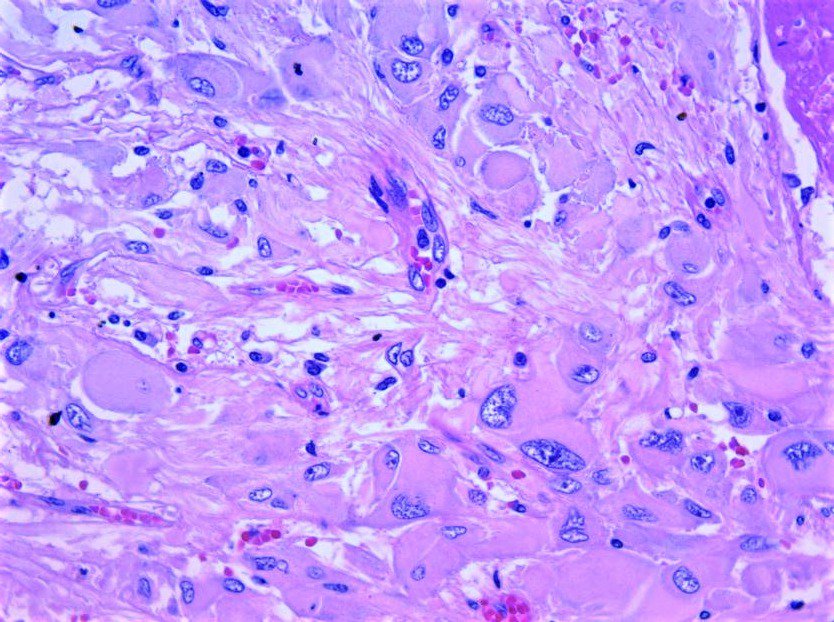

Extradural- spinal lesion in a 50 year old male. What are your differentials? Immunos to come later.

#brain#cns#pathology#neuropath#neurosurgery#surgery#neuropathology